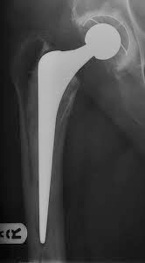

There are two main types of Total Hip

Replacement. Cemented and un-cemented

implants. Both can provide good pain relief and improve

mobility. Cemented implants can loosen in

younger more active patients. The other

consideration is the bearing surface/

articulation of the joint. Ceramic,metal and

polyethelyene can all be used.